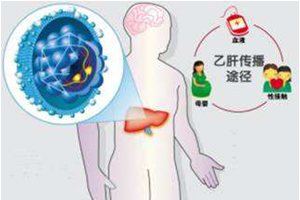

庄辉院士:阻断乙肝母婴传播5要点

庄辉院士:阻断乙肝母婴传播5要点

乙肝病毒表面抗原(HBsAg)阳性母亲生育的新生儿,出生后接受乙肝免疫球蛋白 (HBIG) 和乙肝疫苗联合免疫,母婴传播阻断失败率为5%~10%。

庄辉院士:关于阻断乙肝母婴传播的几个疑问(二)

庄辉院士:关于阻断乙肝母婴传播的几个疑问(二)

HBV母婴传播主要是围生 (产) 期传播,宫内传播的发生率很低。

庄辉院士:关于阻断乙肝母婴传播的几个疑问(一)

庄辉院士:关于阻断乙肝母婴传播的几个疑问(一)

国内外研究均发现,应用替诺福韦酯治疗HBeAg阳性和HBeAg阴性慢性乙肝患者,治疗至12周时,血清HBV DNA水平均降至104IU/ml以下。

乙肝病毒表面抗原(HBsAg)阳性母亲生育的新生儿,出生后接受乙肝免疫球蛋白 (HBIG) 和乙肝疫苗联合免疫,母婴传播阻断失败率为5%~10%。关键字:母婴传播,抗病毒药物,乙肝病毒

庄辉院士:阻断乙肝母婴传播5要点

乙肝病毒表面抗原(HBsAg)阳性母亲生育的新生儿,出生后接受乙肝免疫球蛋白 (HBIG) 和乙肝疫苗联合免疫,母婴传播阻断失败率为5%~10%。关键字:母婴传播,抗病毒药物,乙肝病毒 如何预防药物性肝损伤?

HBV母婴传播主要是围生 (产) 期传播,宫内传播的发生率很低。关键字:母婴传播,抗病毒药物,宫内感染

庄辉院士:关于阻断乙肝母婴传播的几个疑问(二)

HBV母婴传播主要是围生 (产) 期传播,宫内传播的发生率很低。关键字:母婴传播,抗病毒药物,宫内感染 耐药耐药,烦得不要不要(二):为啥耐药?(上)

国内外研究均发现,应用替诺福韦酯治疗HBeAg阳性和HBeAg阴性慢性乙肝患者,治疗至12周时,血清HBV DNA水平均降至104IU/ml以下。关键字:妊娠,HBV DNA,母婴传播

庄辉院士:关于阻断乙肝母婴传播的几个疑问(一)

国内外研究均发现,应用替诺福韦酯治疗HBeAg阳性和HBeAg阴性慢性乙肝患者,治疗至12周时,血清HBV DNA水平均降至104IU/ml以下。关键字:妊娠,HBV DNA,母婴传播